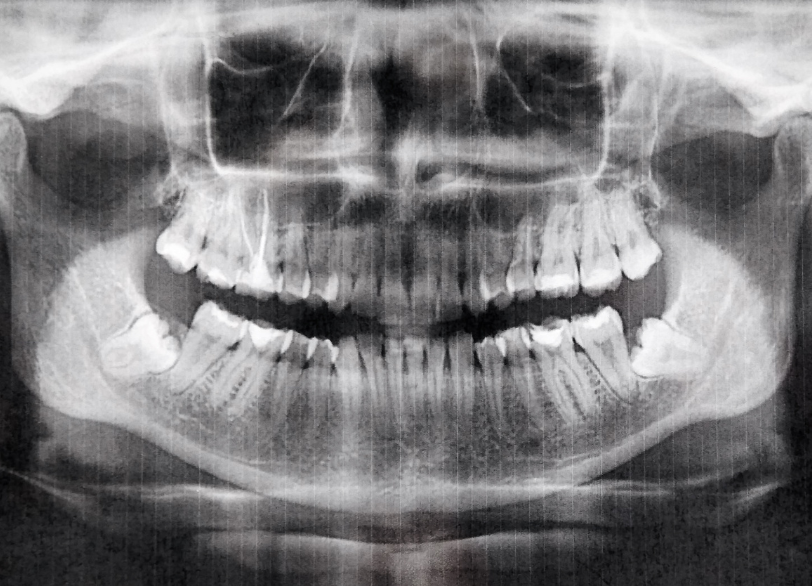

1. デンタルX線装置による正確な診断

親知らずの位置や根の形状、神経との位置関係を把握するために、デンタルX線撮影を行います。

あごの骨や隣の歯との距離を正しく把握することで、抜歯の難易度を判断し、できるだけ負担の少ない方法を選択します。

必要に応じてCTを併用する場合もあり、正確な診断に基づいた安全な治療を心がけています。